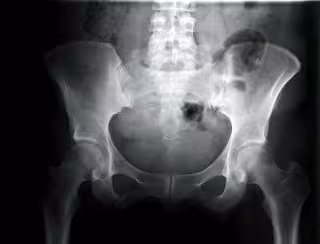

Cadera de mujer vista con rayos.